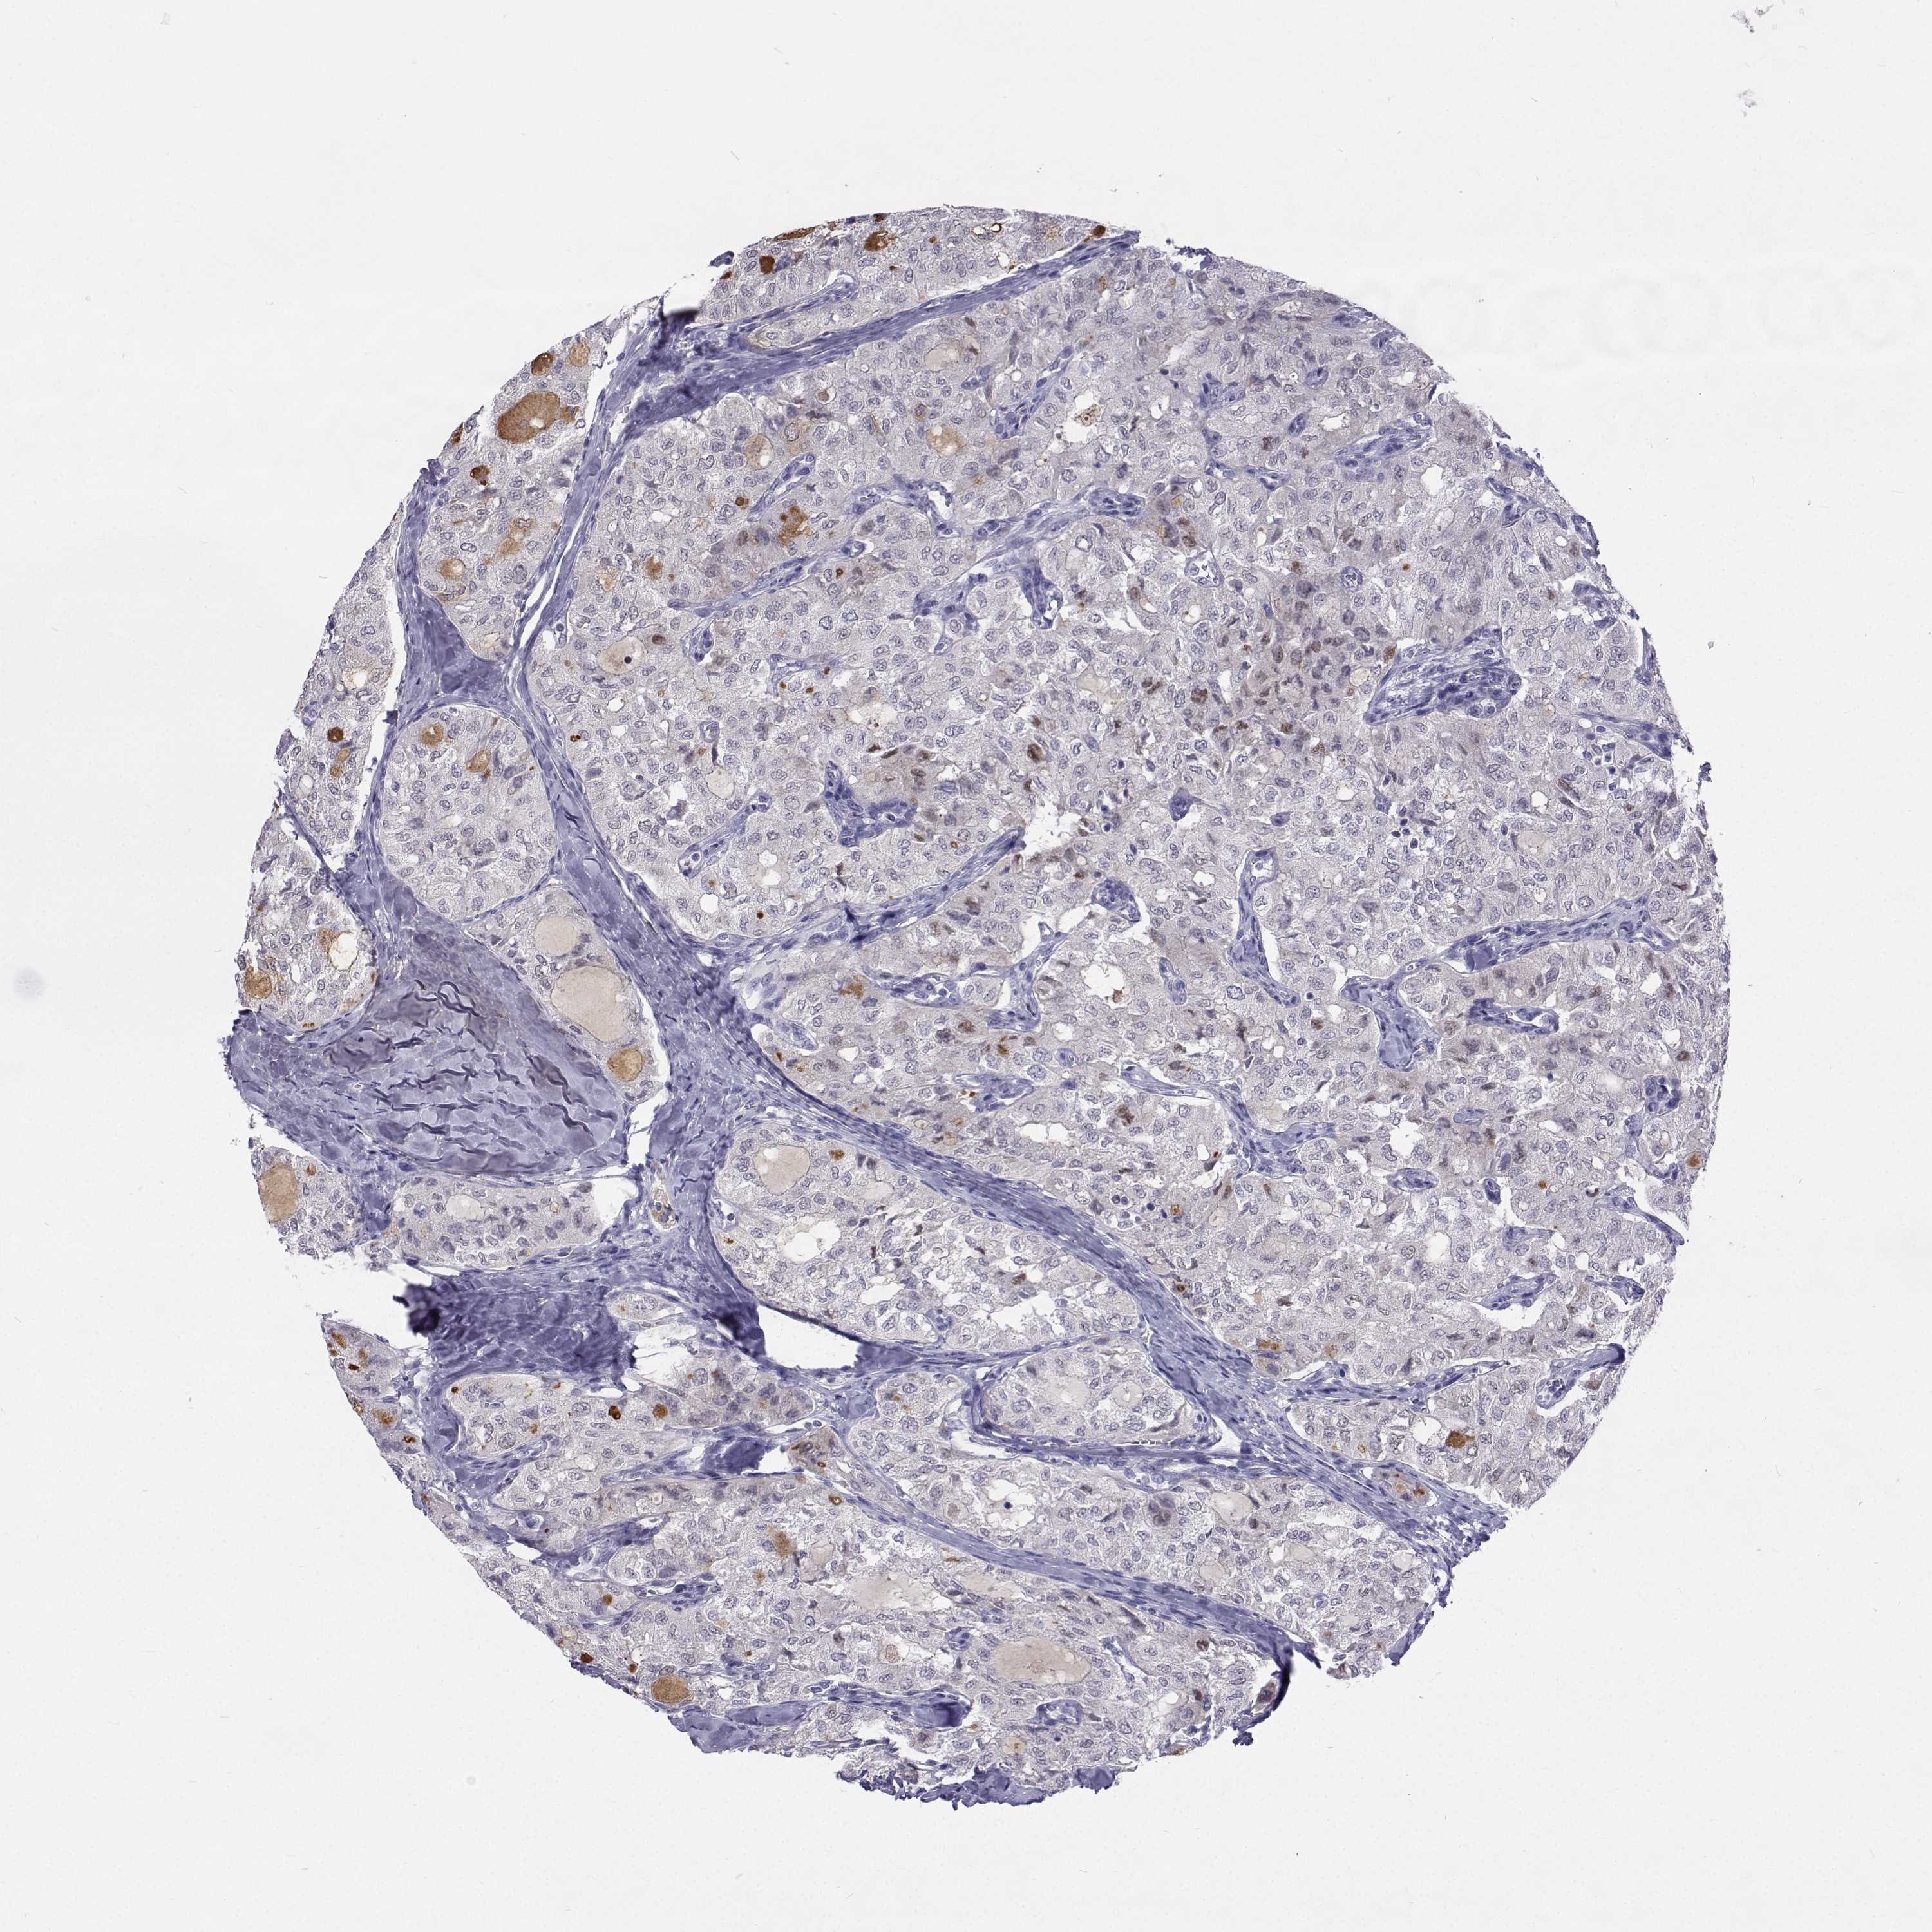

THYROID CANCER - Protein expressioni

A mouse-over function shows sample information and annotation data. Click on an image to view it in a full screen mode. Samples can be filtered based on level of antibody staining by selecting one or several of the following categories: high, medium, low and not detected. The assay and annotation is described here.

Note that samples used for immunohistochemistry by the Human Protein Atlas do not correspond to samples in the TCGA dataset.

Antibody stainingi

Antibody staining in the annotated cell types in the current human tissue is reported as not detected, low, medium, or high, based on conventional immunohistochemistry profiling in selected tissues. This score is based on the combination of the staining intensity and fraction of stained cells.

Each image is clickable and will lead to virtual microscopy that enables deeper exploration of all samples and also displays staining intensity scores, fraction scores and subcellular localization as well as patient and tissue information for each sample.

Antibody HPA035472

Antibody HPA035473

Antibody HPA064835

Staining

High

Medium

Low

Not detected

Intensity

Strong

Moderate

Weak

Negative

Quantity

>75%

75%-25%

<25%

None

Location

Nuclear

Cytoplasmic/membranous

Cytoplasmic/membranous,nuclear

Papillary adenocarcinoma, NOS

Follicular adenoma carcinoma, NOS